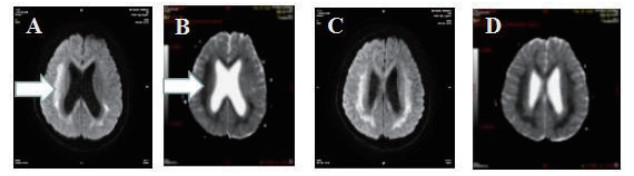

2 结果 2.1 基本资料及头颅核磁特征本观察研究最终纳入患者51例,中毒患者的头颅核磁特征表现为:在MRI的常规序列(T1\T2\FLAIR)病灶显示不明显,但在DWI表现为高信号,ADC值下降呈低信号。病变部位主要是胼胝体的压部(所有阳性病例胼胝体压部均受损),病变也可以形成以胼胝体为中心的广泛白质病变,皮质不受损害。见图 1,2。

| 图 2 A\C弥散像呈高信号,B\D ADC图呈低信号(箭头所示) |

3 讨论氟乙酰胺进入人体后生成氟柠檬酸, 可在脑组织诱发细胞毒性脑水肿[4]。细胞毒性脑水肿在DWI上呈现高信号,在ADC上呈低信号,结合我们发现佐证氟乙酰胺中毒所引起的脑部病变性质是细胞毒性脑水肿,并且证实氟乙酰胺中毒病变部位主要是胼胝体的压部,病情危重者可出现以胼胝体为中心的广泛白质病变,皮质不受损害。所幸此病变特点符合可逆性胼胝体压部病变综合征(reversible splenial lesion syndrome,RESLES)[5]:是一种由各种病因引起的累计胼胝体压部的临床影像综合征。其特点为MRI上可见胼胝体压部(SCC)的卵圆形、非强化病灶,一段时间后可完全消失[6]。